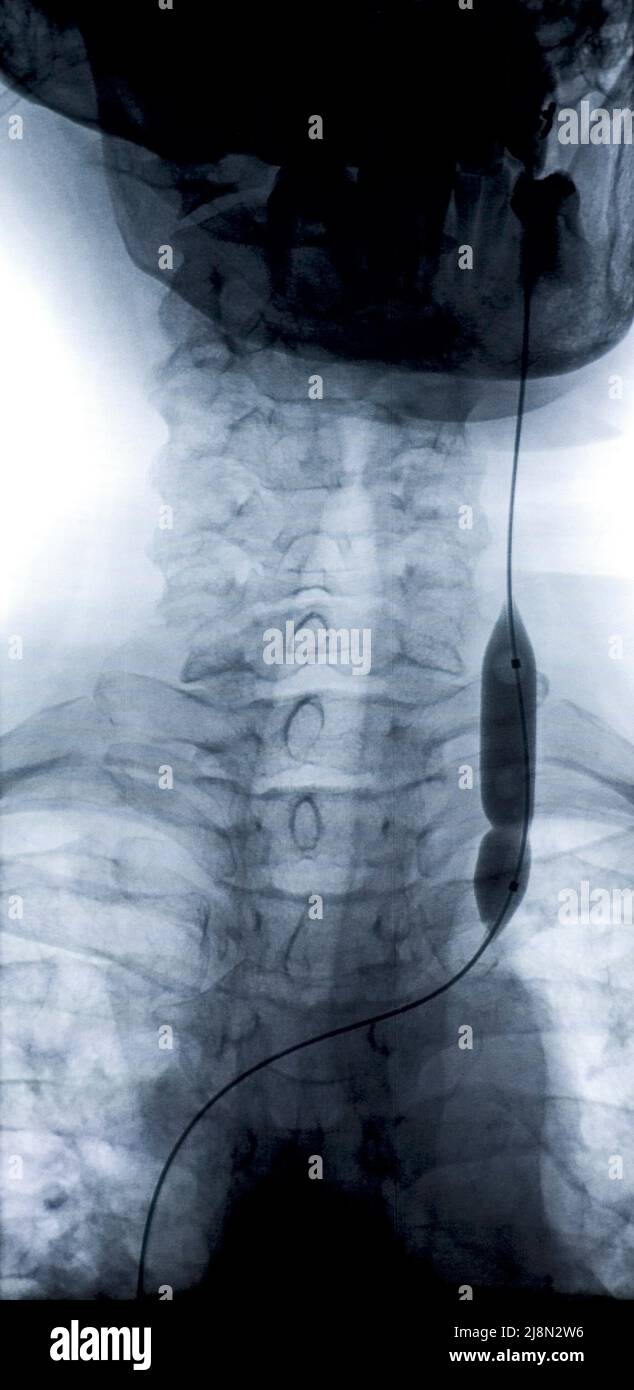

Aug 9, 2010. Balloon catheter use in coronary angioplasty seen in the x Jugular Vein Catheter X Ray In essence, the practitioner creates the landmarks required for the successful insertion of a central venous catheter by properly positioning their left three. Cvcs are most commonly inserted via the right internal jugular vein. There are three main access sites for the placement of central venous catheters, namely internal jugular, common femoral, and subclavian veins. A combination of lung ultrasonography,. Jugular Vein Catheter X Ray.